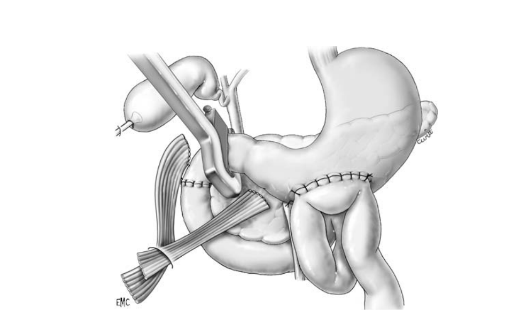

Phẫu thuật Patch tá tràng – Patch technique

A – Tổn thương rộng ở D2, lộ bóng Vater

B – Đưa quai hỗng tràng lên úp vào vết thương D2 kiểu Roux-en-Y

Phẫu thuật cắt bỏ một phần tá tràng

A- Vỡ D3 độ III (AAST) ngay sát bó mạch mạc treo tràng trên

B- Cắt đoạn D4, nối hỗng tràng với D2 Roux-en-Y